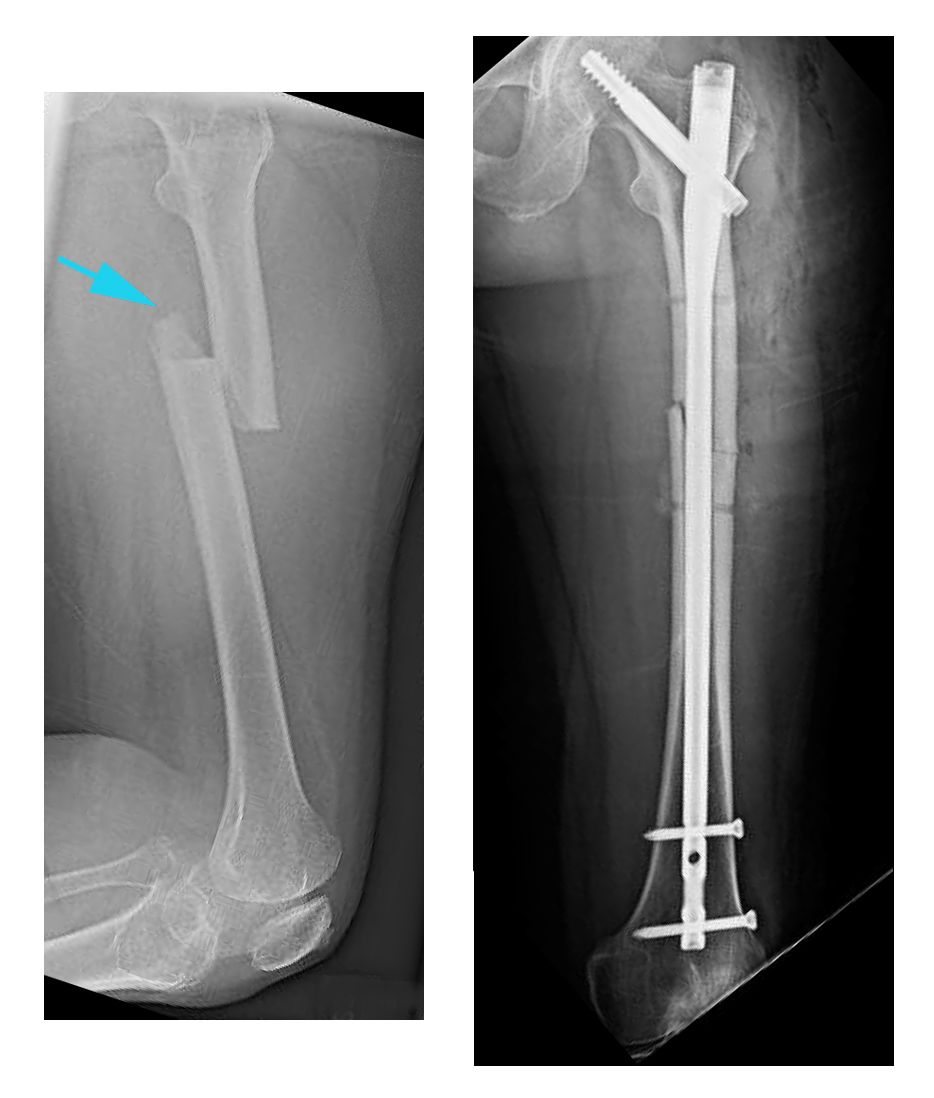

Clavos intramedulares. Actualmente, la utilización de clavos intramedulares es el método que la mayoría de los cirujanos usan para tratar fracturas de la diáfisis femoral. Durante el procedimiento, se introduce una barra metálica especialmente diseñada en el canal del fémur. Esta barra atraviesa la fractura para que se mantenga en su posición.

Los clavos intramedulares ofrecen una fijación fuerte, estable y de extensión total.

Puede introducirse un clavo intramedular en el canal de la cadera o la rodilla. Los tornillos se colocan por encima y por debajo de la fractura para mantener la pierna alineada correctamente mientras el hueso se repara.

Los clavos intramedulares suelen estar fabricados con titanio. Vienen en varios tamaños y diámetros para adaptarse a la mayoría de los fémures.

(Izquierda) Esta radiografía, tomada de perfil, muestra una fractura transversal del fémur. (Derecha) En esta radiografía frontal, la fractura se trató con clavos intramedulares.